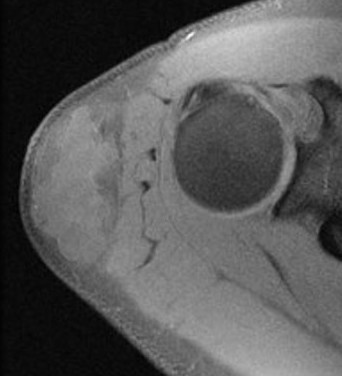

MRI

Deep to fascia / heterogenous

Liposarcoma vs Atypical Lipoma

Liposarcoma

- > 5 cm

- rapidly growing

- deep to fascia

- non homogenous on MRI